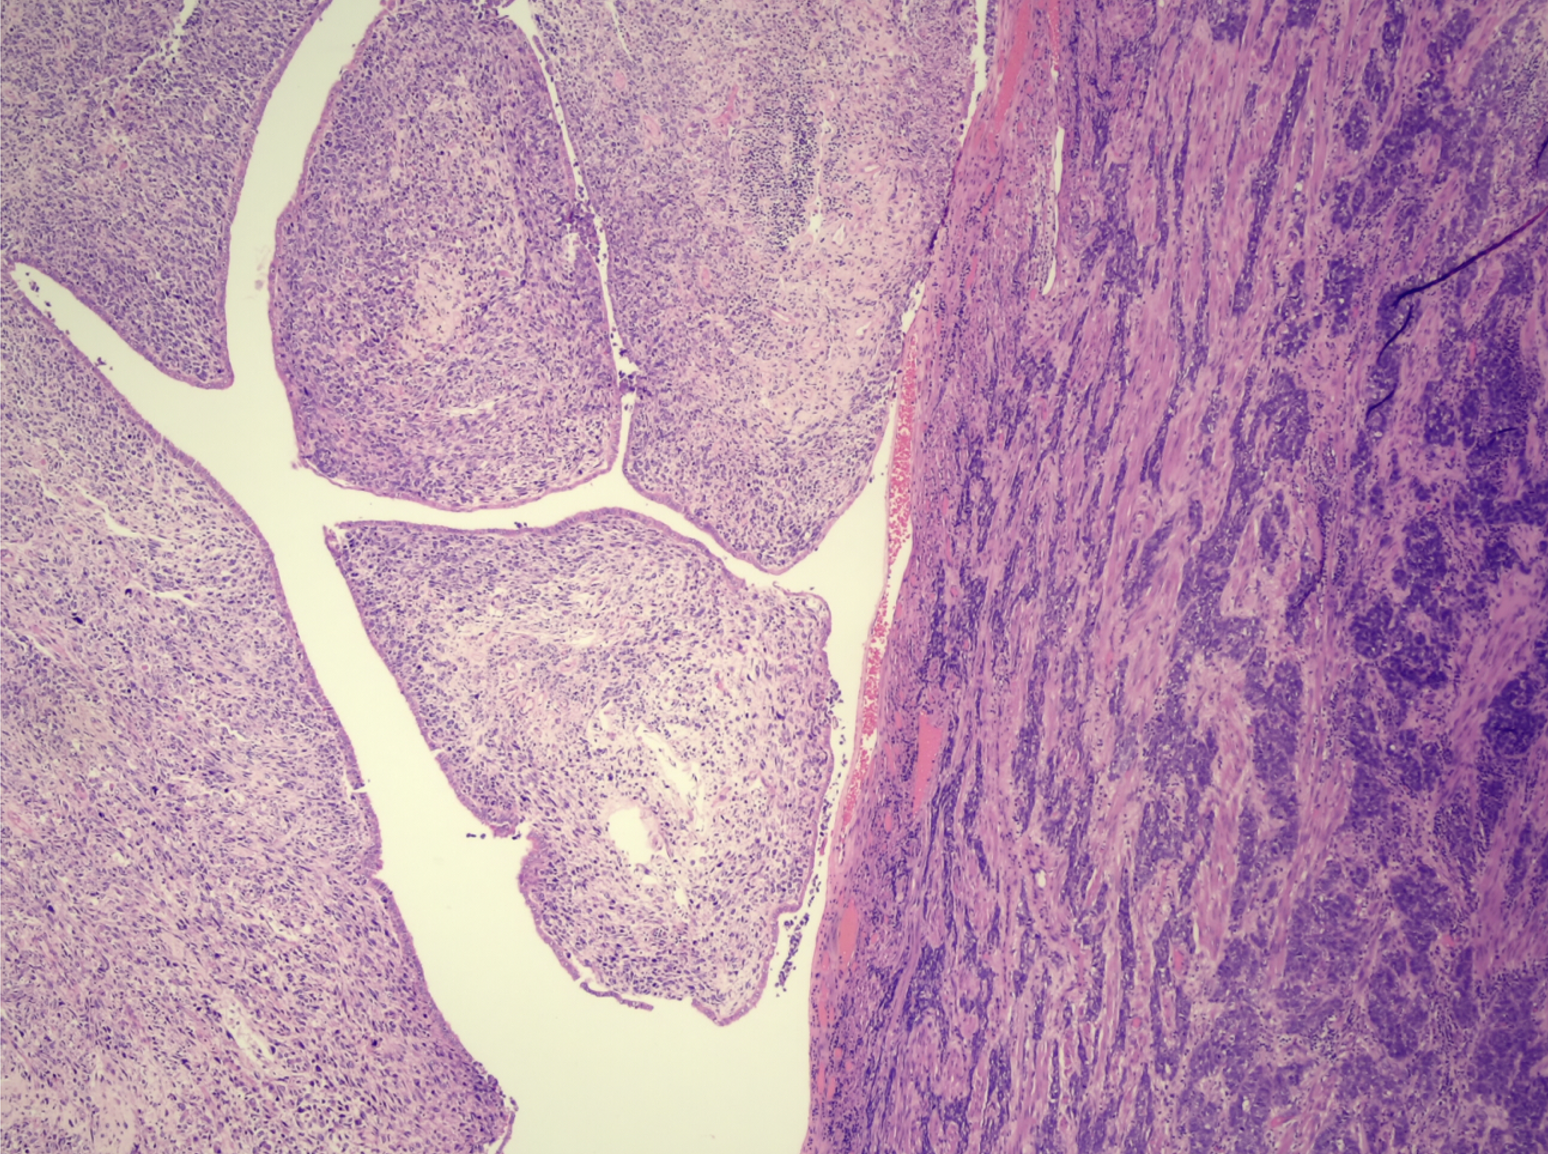

Con este diagnóstico preoperatorio se realizó manejo quirúrgico con histerectomía y salpingooforectomía bilateral, con omentectomía parcial por laparotomía con márgenes de resección libres de tumor. El reporte de patología informó la presencia de tumor de colisión conformado por un adenocarcinoma endometrial de tipo seroso papilar de alto grado, estadio II, y de adenosarcoma cervical, con elementos heterólogos rabdomioblásticos y sobrecrecimiento estromal casi del 100 % correspondiente al 60 % de la pared cervical, estadio IB2 (Figuras 1 y 2), con marcación inmunohistoquímica característica de cada tipo histológico (Figuras 1 a 3 y Tabla 1). Este tumor no fue identificado en las imágenes diagnósticas.